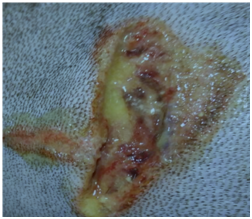

Clinical application of copazan herbal gel with beepolis

(Figure 4-6).

Figure 4 Before treatment with copazan herbal gel with bee polis.

Figure 5 Treatment with copazan herbal gel with beepolis (3x a day, open wound, protective collar used on the animal).

Figure 6 Treatment results after 72 hours with copazan herbal gel with bee polis.